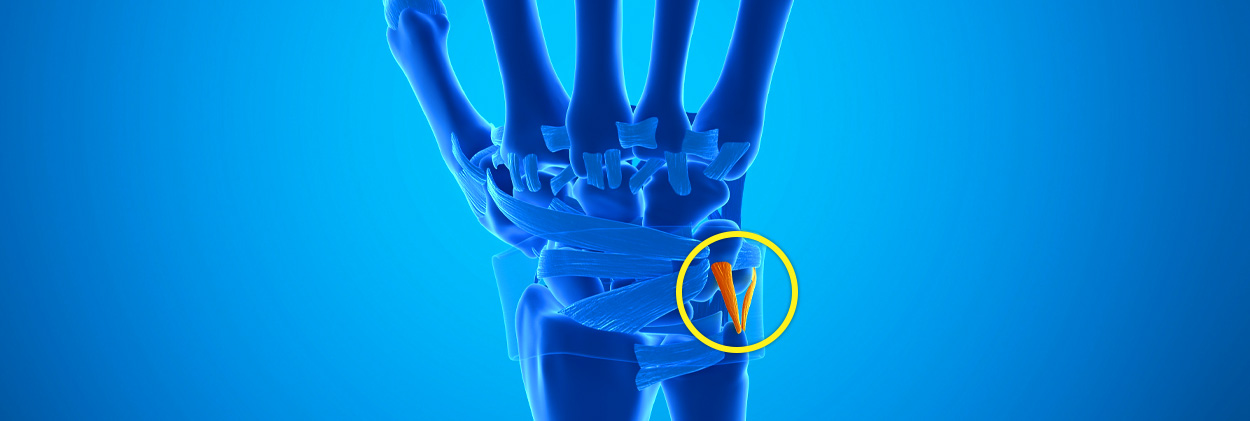

손목의 새끼손가락 쪽에 위치한 삼각형 모양의 연골 및 인대 복합체이며, 손목 관절의 안정성 유지 및 충격 흡수의 역할을 합니다.

또한 요골과 척골 사이의 움직임을 조절하고, 손목의 회전 운동을 보조합니다.